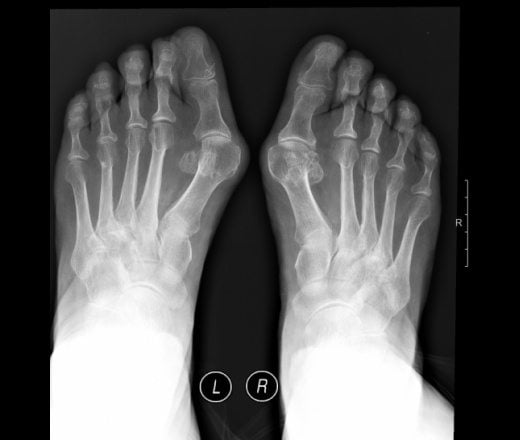

Диагностика

Как лечить артрит на пальцах ног? Лечение зависит от типа заболевания, его признаков и симптомов. Задача специалиста – правильно диагностировать патологию. Диагностика проводится врачом-ревматологом на основе изучения истории возникновения, тяжести симптомов, физического обследования, клиническо-лабораторных исследований и инструментальных тестов:

- рентгенография;